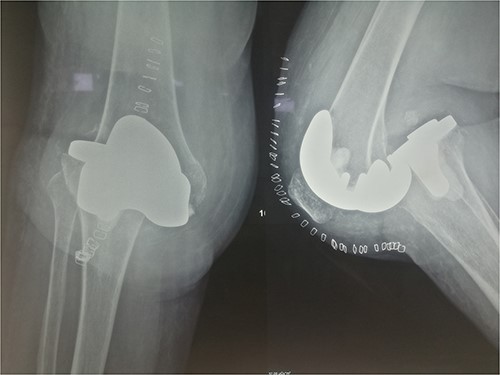

The patient underwent a medial-pivot design TKA (Evolution Medial-Pivot Knee System, Microport, China). Intraoperatively, a full ROM was achieved only after extensive soft tissue and bone releases. The extension gap was limited by significant hamstring spasticity, and a proper extension gap was attained after additional anterior femoral cut. Early postoperative recovery was uneventful (Fig. 2). On the third postoperative day, the patient complained of severe knee pain accompanied by excessive swelling during kinesiotherapy. Clinical examination showed a posterior sag sign at 30° of flexion (Fig. 3). No signs of neurovascular deficit were obvious. A knee X-ray revealed posterior TKA dislocation and a small, non-displaced femoral fracture (Fig. 4). The tibial component was reducible, but redislocation occurred with the knee extended over 90°, indicative of severe instability. Laboratory investigations, including erythrocyte sedimentation rate and C-reactive protein, were normal. A knee arthrocentesis was performed with no substantial findings. Two botulinum toxin injections (200 IU) to the hamstrings were performed without improvement. Local muscle hypertonia was evaluated through a neurological examination and a brain computed tomography scan, with no remarkable findings. The patient’s history included intramedullary nailing of the right femur due to an intertrochanteric fracture 8 months before the TKA.

Clinical presentation of tibiofemoral dislocation following TKA.